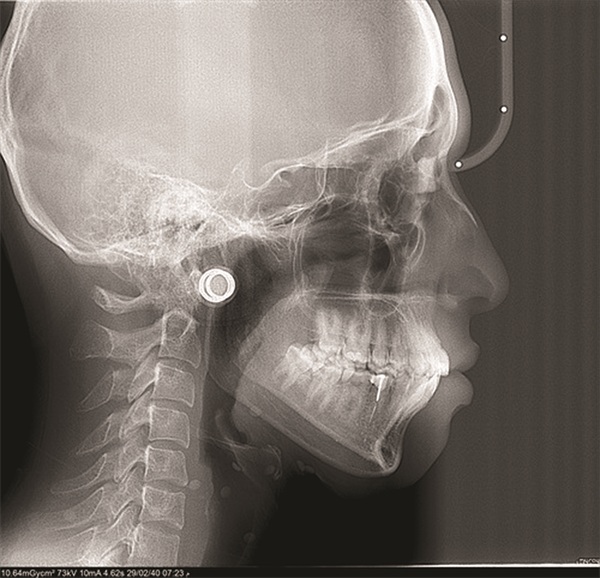

The diagnostic findings told a more complicated story. The patient presented with a skeletal Class II relationship, bilateral Class I molar and canine relationships, collapsed arches, and proclined incisors in both arches. Both midlines were shifted to the right. She also exhibited crossbite of the upper right first molar and upper right lateral incisor, a discrepancy between centric relation and centric occlusion, and a noticeable cant in the lower anterior segment. Her dental history included previous extractions of the upper right third molar and upper left second molar (Figs. 1–12).

Fig. 1